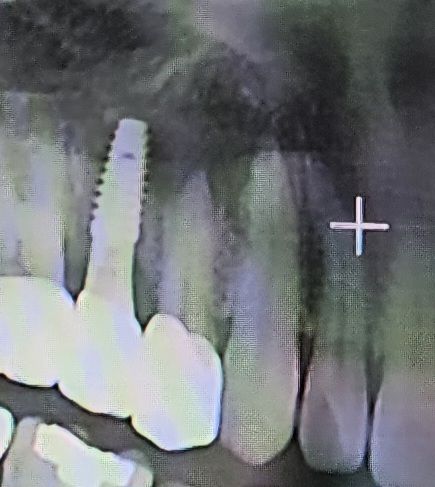

14개월 전쯤 나란히 놓여있는 치아 2개를 치료받았습니다. 앞쪽치아는 신경치료없이 지르코니아로 크리운 치료를 했구요, 뒷쪽 치아는 임플란트 치료를 했습니다. 1년정도 사용중 잇몸부분 염증이 있는것 같아 내원했더니 앞쪽치아의 뿌리부분에 염증이 생겨 크라운을 뜯어내고 신경치료 후 다시 지르코니아 크라운을 진행한다고 하며 보증기간내에 해당한다며 지르코니아20M 기둥 5M 신경치료비용 5M을 요구합니다. 지식인등을 찾아보면 크라운 자체에 틈이있거나 하면 세군이 침투하며 염증발생할 수 있다고도 하는데.. 양치, 치실, 워터픽까지 사용하면서 잘 관리했는데 치료비용을 이중으로 청구한다고 하니 억울한 생각이 많이 듭니다. 이렇게 저렴하게 해주는것처럼 치과의 과실을 덮어버리는 것같은 느낌이 계속드네요. 일반적으로 이렇게 진행되는것이 맞나요~? 도와주세요ㅠㅠ

일반 현재 사진만으로는 정확한 판단이 어렵습니다. 보여주신 사진은 panorama 사진으로 전체 치아를 보는데 효과적이나 해당 부분을 구체적으로 보는데는 한계가 있습니다. 다만 치아 뿌리에 염증이 있다고 했다면 치료를 하는 것이 맞으나 이러한 염증이 단순히 크라운 자체에 틈이 있다고 생기는 것만 아니며 다양한 원인으로 발생할 수 있습니다.